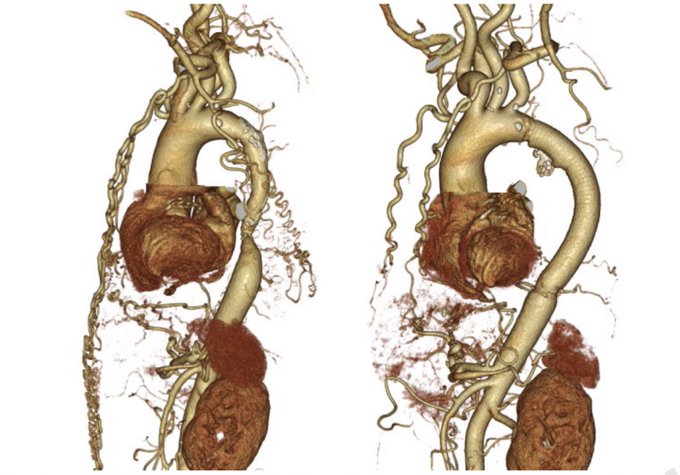

流体力学解析x 大動脈手術が論文化!

第一弾は成人の大動脈縮窄症で最もエナジーロスが少ないバイパス法はどれか!?

患者の術前CTを使って最適な方法をオーダーメイドして手術する。未来の手術がもうそこまで